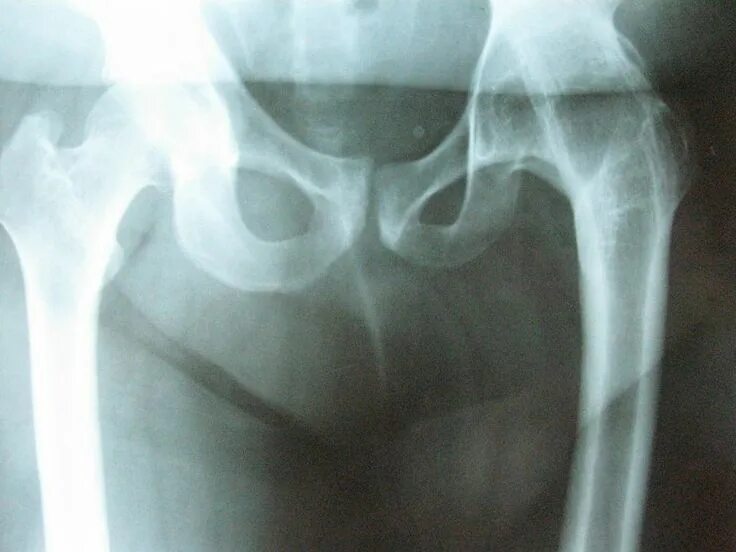

Доа тазобедренных суставов 1 степени что это